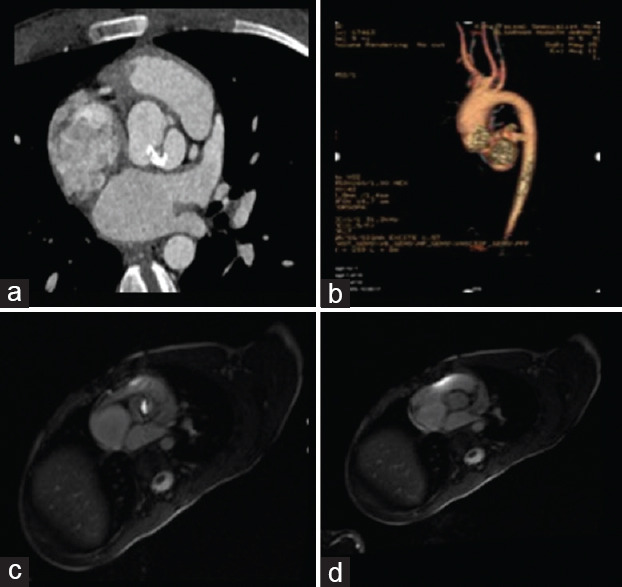

This article provides comprehensive insights into the evaluation of simple congenital heart diseases (CHDs) in adults, emphasizing the pivotal role of echocardiography. By focusing on conditions such as congenital aortic stenosis, aortic coarctation, patent ductus arteriosus, atrial septal defects (ASDs), and ventricular septal defects (VSDs), the review underscores echocardiography's intricate contributions to precise clinical decision-making. Echocardiography serves as the primary imaging modality, offering high-resolution visualization of anatomical anomalies and quantification of hemodynamic parameters. It enables tailored therapeutic strategies through its capacity to discern the dimensions, spatial orientation, and dynamic shunt dynamics of defects such as ASDs and VSDs. Moreover, echocardiography's advanced techniques, such as tissue Doppler imaging and speckle tracking, provide detailed insights into atrial mechanics, diastolic function, and ventricular filling kinetics. Integration of echocardiographic findings into clinical practice empowers clinicians to create personalized interventions based on quantified ventricular function, which spans systolic and diastolic aspects. This approach facilitates risk stratification and therapeutic planning, particularly pertinent in heart failure management within the CHD patient population. In summary, echocardiography transcends its role as an imaging tool, emerging as a precision-guided instrument adept at navigating the complexities of simple CHD in adults. Its ability to expedite diagnosis, quantify hemodynamic impacts, and unravel multifaceted functional dynamics culminates in a comprehensive depiction of these conditions. The fusion of these insights with clinical expertise empowers clinicians to navigate the intricate pathways of CHD, crafting tailored therapeutic strategies characterized by precision and efficacy.